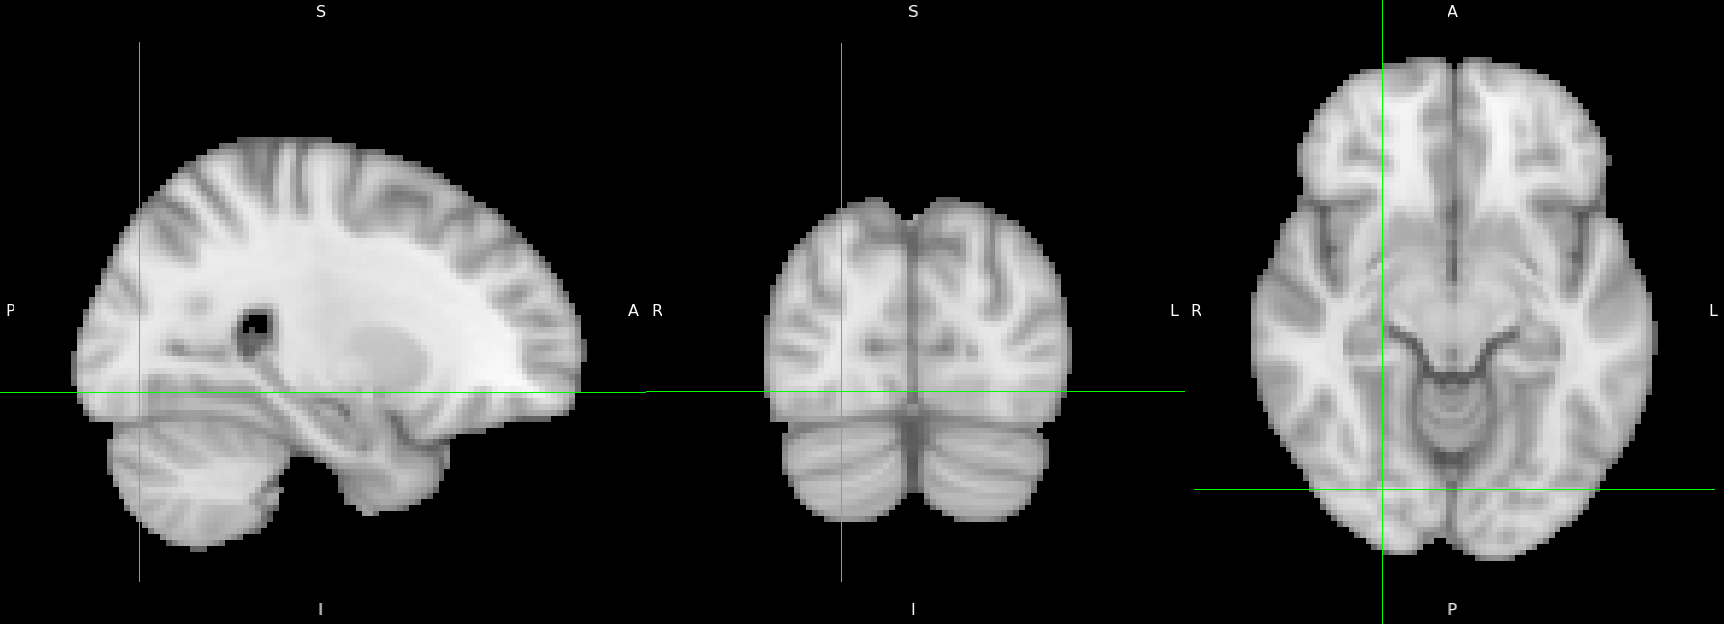

As an example, we show results from a single simulation run with . Figure 5 shows the -value map obtained for a single subject. Figure 6 contains results obtained from the three methods, merging information from all subjects.

Evidently, AdaFilter can not control the overall FDR in this scenario. We observe from Figures 6 that in all the three dimensions, our proposal has better activation detection power than Benjamini et al. (2009): the proposed method discovers the highest number of voxels for very high values of (i.e., is 6 or 7). One reason behind the superior performance of our proposal is its removal of the conservative PC -values before applying the multiple testing procedure.